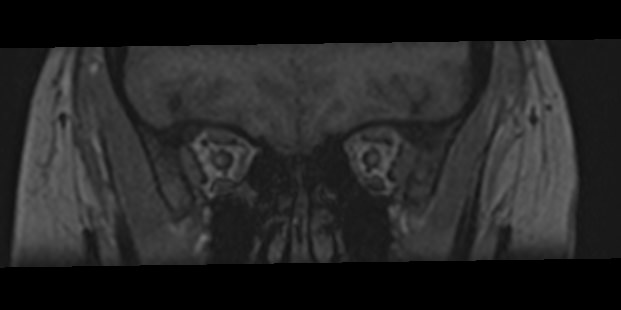

МРТ глазных орбит является современным способом диагностики патологии глазниц, в которых расположены глазные яблоки и их придатки (окружающая жировая клетчатка, зрительные нервы, слезные железы, мышцы глаза, связочный аппарат, кровеносные сосуды). МРТ орбит также позволяет получить детальную информацию о состоянии мягких тканей периорбитальных областей (тканей, окружающих глазницу).

Магнитно-резонансную томографию назначают при необходимости детального изучения мягкотканных структур глазниц. В результате исследования получают срезы анатомической области, на которых можно рассмотреть мельчайшие элементы. МРТ орбит обеспечивает визуализацию следующих структур:

• элементы глазного яблока, включая оболочки;

• периорбитальная клетчатка;

• мышечный аппарат;

• зрительный нерв;

• слезные железы.

Ангиорежим позволяет изучить сосуды глаза (глазная артерия и вены сетчатки).

• эндокринная офтальмопатия;